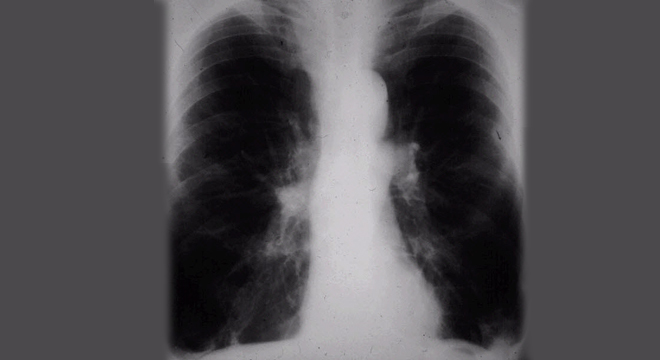

Lungenmphysem: Röntgenbild der Lungen

• Röntgenuntersuchung und Computertomographie der Lungen